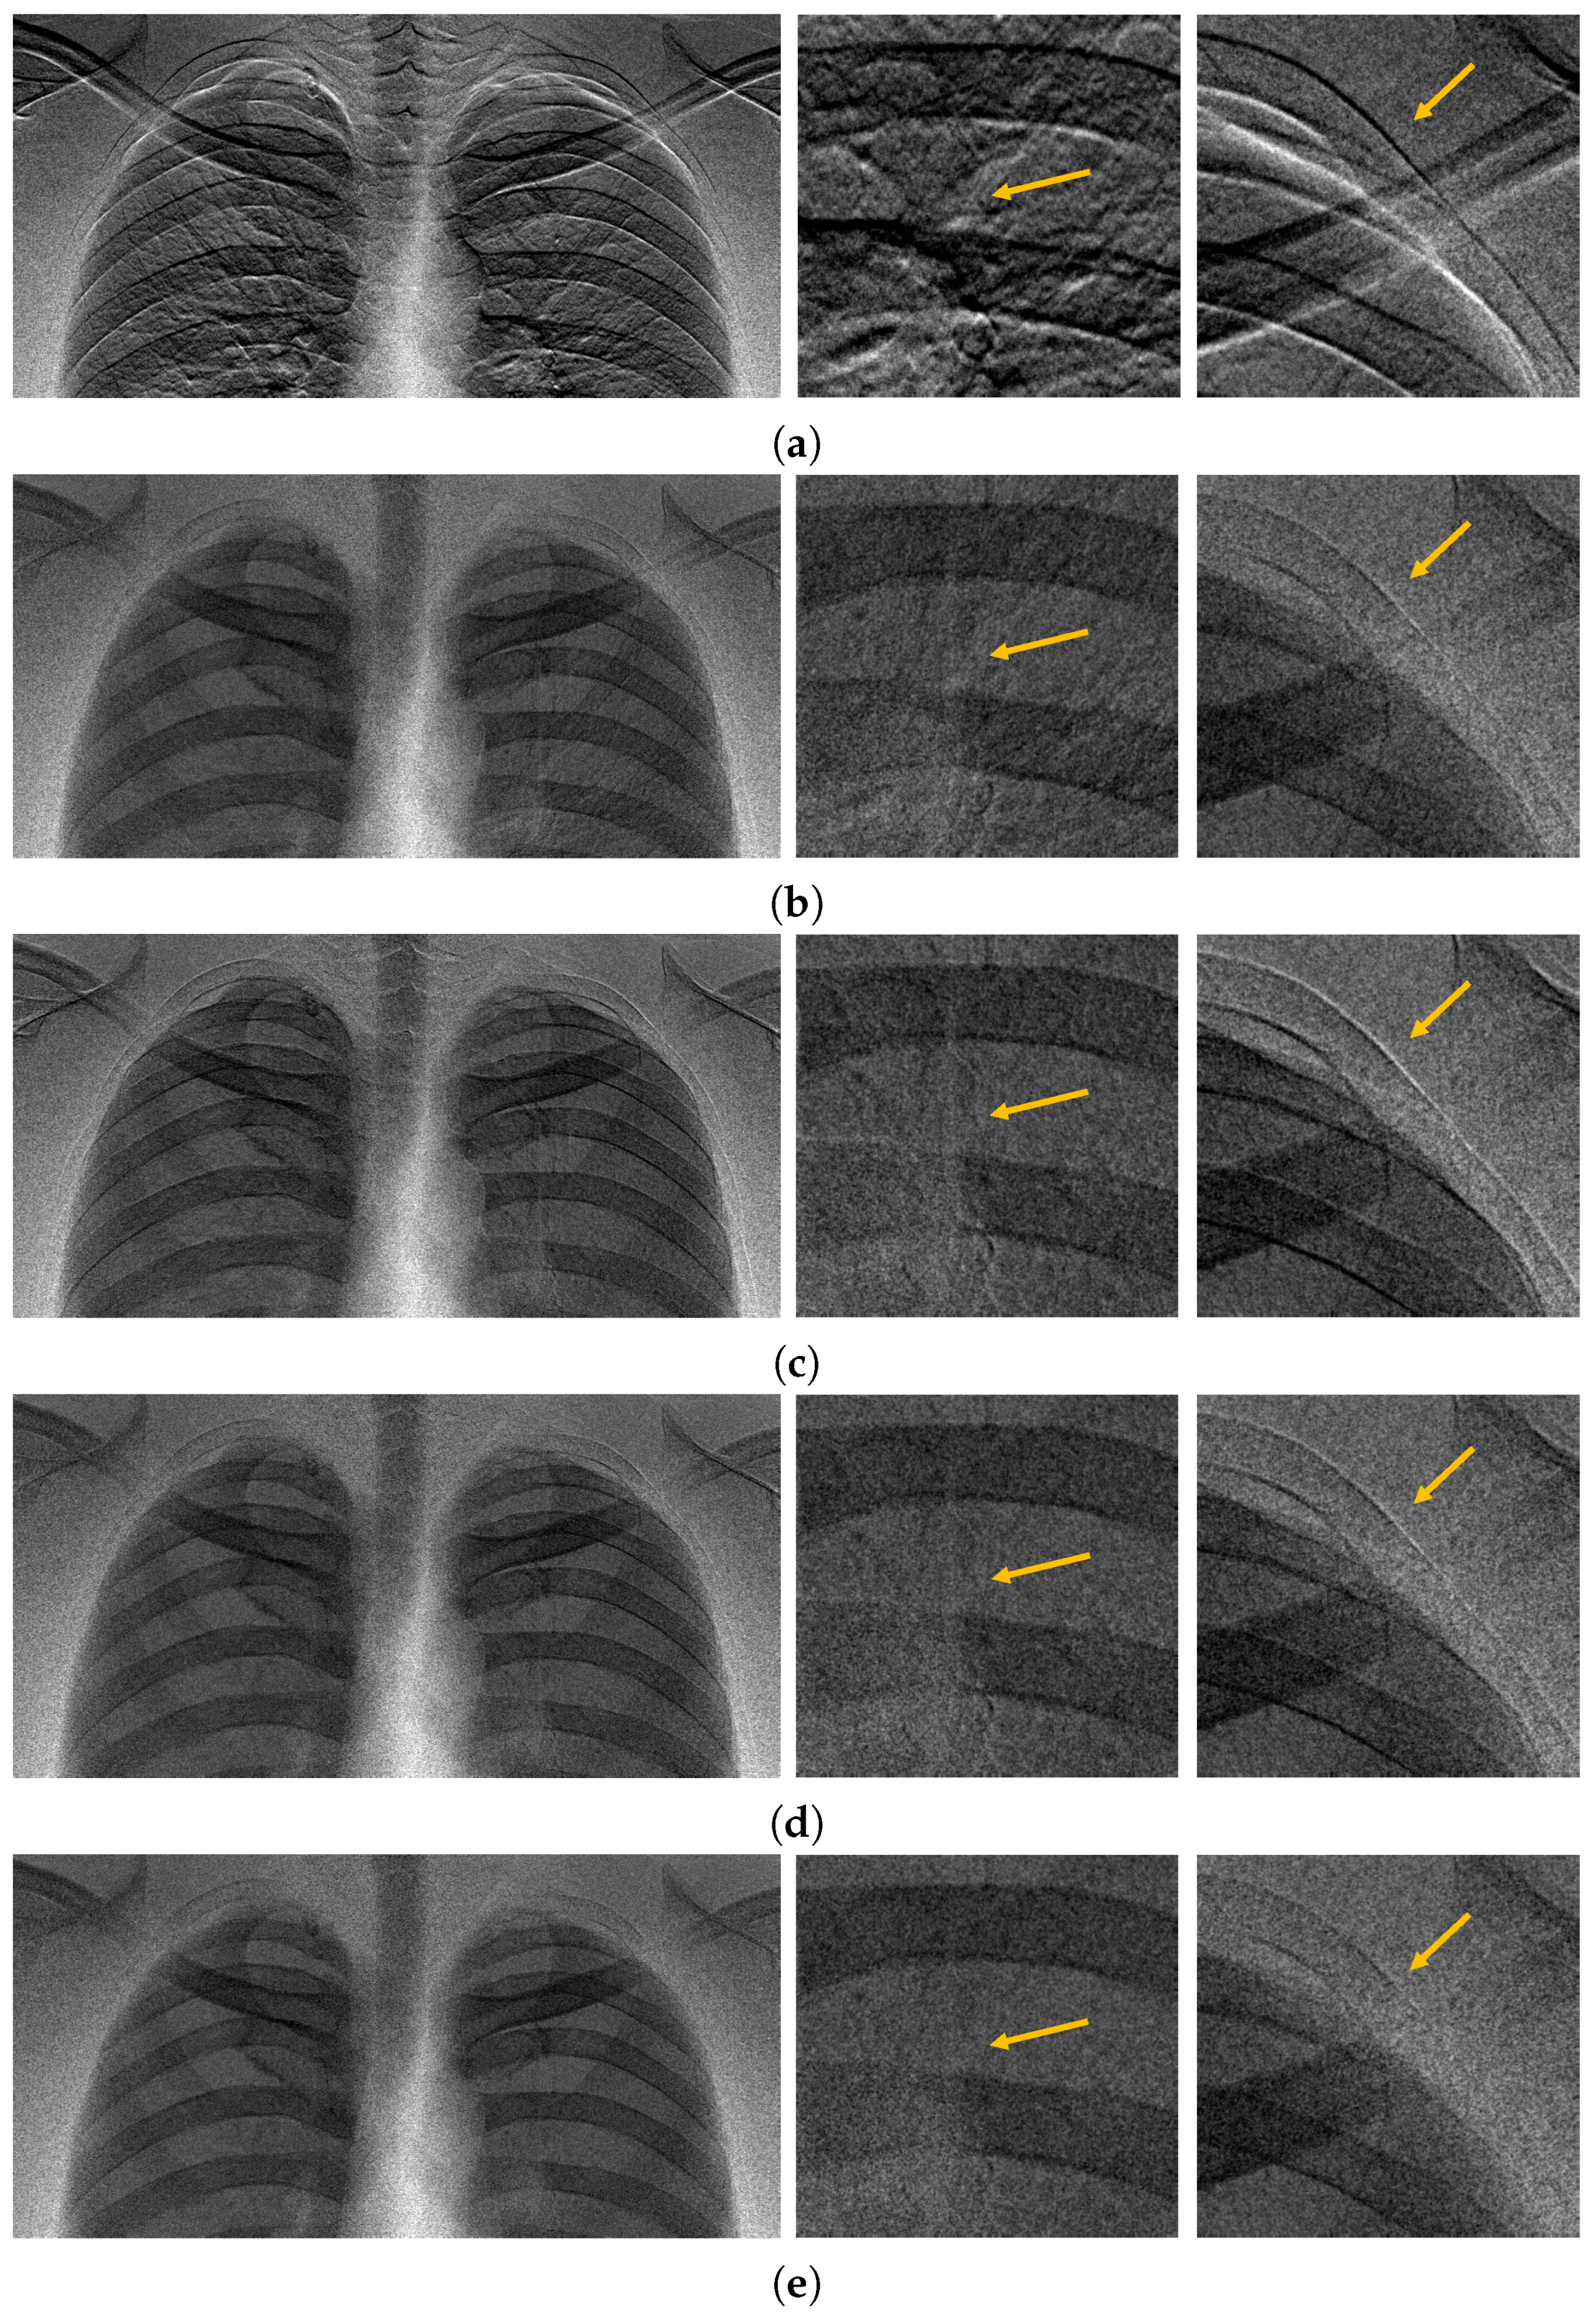

3.2. Registration Example of the Chest X-Ray Images